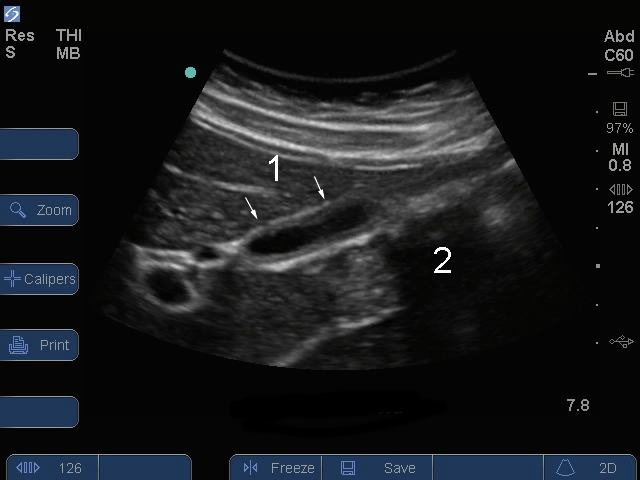

胆嚢縦断面食後画像

S シリーズ: 胆嚢縦断面食後

食後の胆嚢

腸内ガス